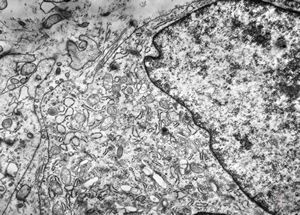

M,40y. | granular cell tumor

F,30y. | granular cell tumor